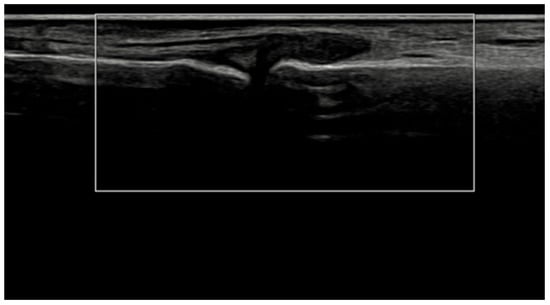

Figure 7.

Ultrasound images of the elbow extensor enthesis at baseline (T0, top image) showing power Doppler signal (PD grade 2), and at 3 months (T3, bottom image), demonstrating resolution of power Doppler signal (PD grade 0).